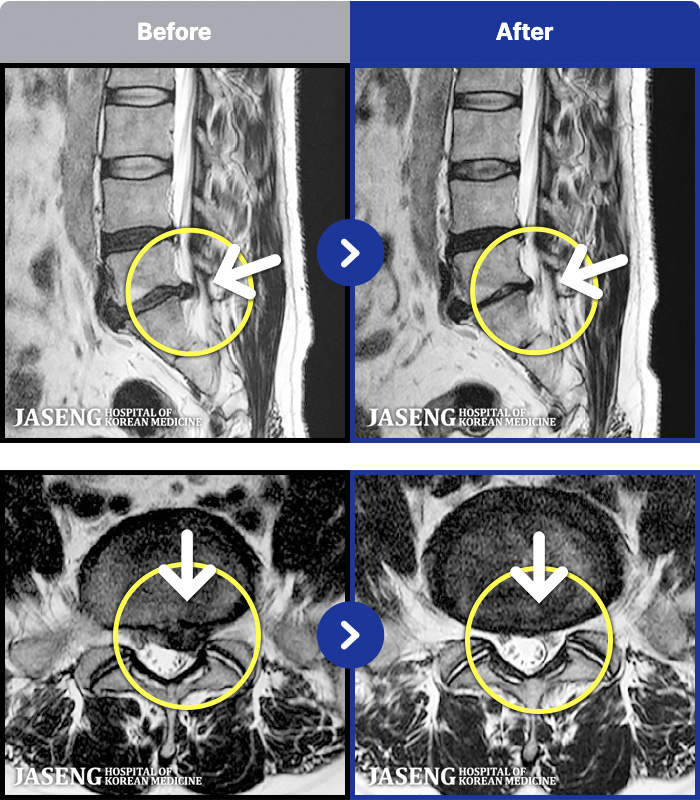

MRI ġ

1,240 MRI ũ ʸ Ȯϼ.